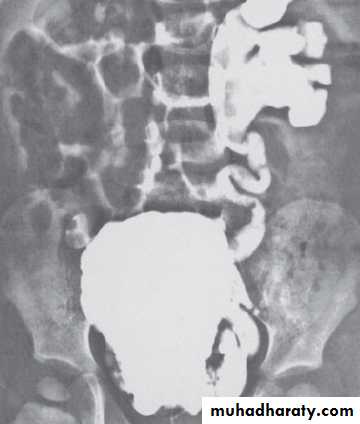

U.S. , IVU, MCUG( it shows the valve folds, the trabeculated bladder with diverticulae & even vesicoureteral reflux).